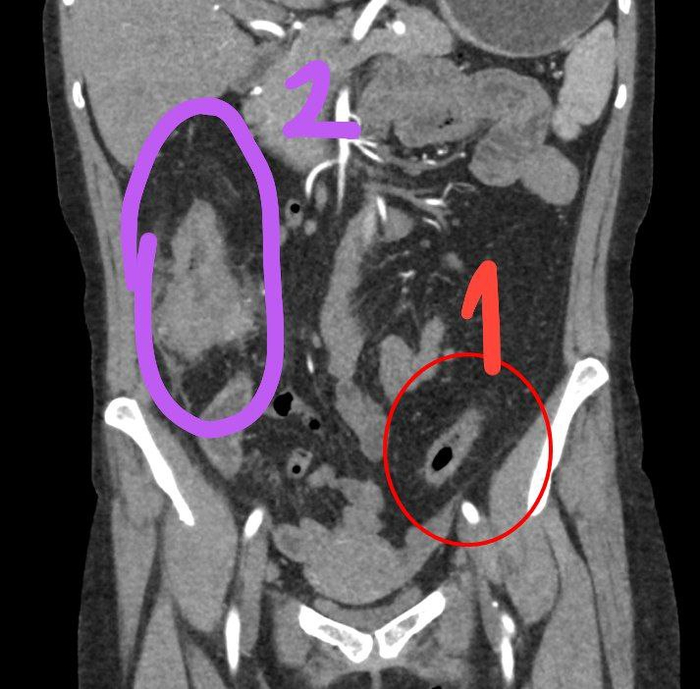

Документы из дела. Молодая красивая женщина. Язвенный колит более 20 лет, лечение периодическое. При очередном обследовании выявлен стеноз (сужение) сигмовидной кишки, при этом никакой опухоли не было видно. Биопсия "на всякий случай" - аденокарцинома. По КТ "ничего не видно", кроме воспалительного инфильтрата в правых отделах, куда не смогли дойти эндоскописты из-за стеноза. Такую картину я уже видел, к сожалению, и тогда был не готов к последующему ужасу... Это так прячется рак на фоне колита. В общем, у меня личные подозрения были, но доказательств пока нет.

Поэтому пошёл классически, через лапаротомию. В куполе слепой кишки сидела опухоль (к диагностам потом сходил и рассказал в порядке обратной связи). Убраны все лимфоузлы (некоторые до 2 см!), сосуды очищены, D3 лимфодиссекция по всем направлениям. И тонкокишечный резервуар, который был успешно подшит на место. На время его заживления выведена временная стома на пару месяцев. Всё нужное сохранено, всё лишнее удалено.